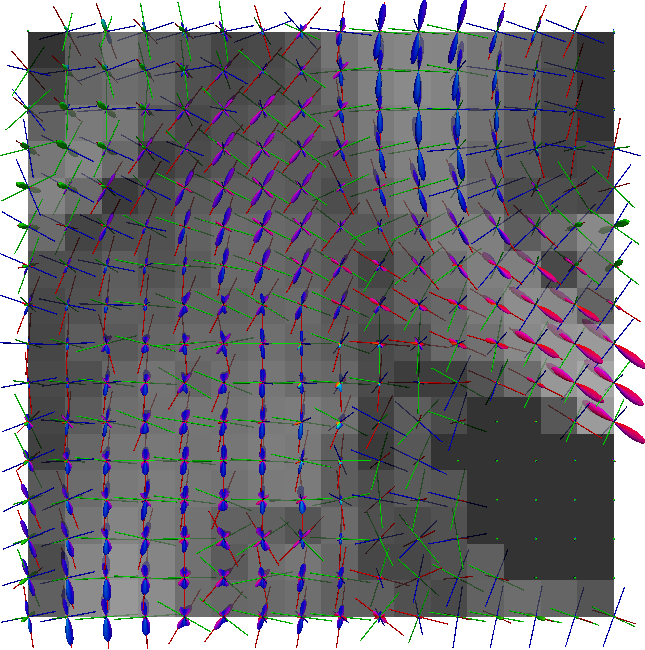

Non-negative spherical deconvolution (NNSD) (Cheng et al., 2014) is performed to estimate non-negative fiber ODFs from three-shell DWI data. NNSD works for multi-shell data. It is more robust to noise, and the obtained fiber ODFs (fODFs) in isotropic regions are closer to the isotropic spherical PDF, compared with conventional constrained spherical deconvolution (Tournier et al., 2007). After obtaining the fODFs by NNSD, the peaks are detected from the estimated fODFs with GFA larger than , as described in Section 3.4. OO and OD are calculated from the spherical harmonic representation of fODFs along their principal peaks as shown in Algorithm 1. The second row in Fig. 11 demonstrates FA from tensors estimated by DTI, OO and OD from fODFs estimated by NNSD, and the total distortion map estimated from the local orthogonal frames of fODFs. Fig. 12 and 13 show the close-up views of fODFs, local orthogonal frames, and the six proposed indices for the red and blue regions in Fig. 11, where the region shown in 12 is also visualized in the DFA pipeline in Fig. 1. The fODF glyphs are colored by using its sampled directions. The three orientations in the local orthogonal frame in each voxel are visualized by using three tubes in red, green, and blue colors respectively. There is no local orthogonal frame in some voxels because those voxels have GFA values lower than . These figures show the following: 1) OO is high in anisotropic areas with well-aligned directions, while OD is high in isotropic or crossing areas. 2) The four orientational distortion indices are low in areas with well aligned principal directions, and zero in isotropic voxels without peaks. Distortion indices are high in voxels where the principal directions in its local neighborhood change largely. 3) The central voxels in red region is the crossing area of the Corpus Callosum from left to right and Fornix that goes through the coronal slice. The twist index showed high value in this crossing area as expected.